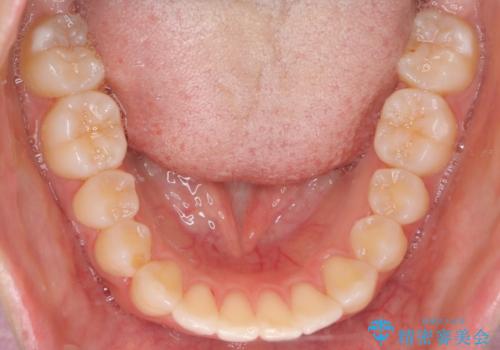

前歯のがたつきをインビザラインで目立たない矯正

- 上下の前歯のがたつきを主訴に来院されました。

マウスピースでの矯正を希望されたので、インビザラインで矯正治療を行うこととしました。